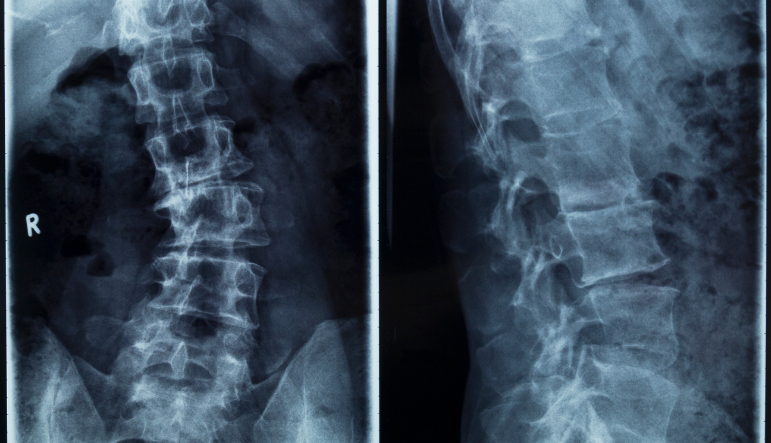

If your healthcare provider suspects scoliosis, they will likely take an X-ray. This picture will show the position of the bones of your spine, and the degree of curvature can be measured. Some people have an “S” curve; their lower lumbar spine curves one way, and their middle thoracic curves in the opposite direction. Others have a “C” curve where the lumbar and thoracic spine curve in one direction together.

As your spine curves laterally, the vertebra rotates slightly. Many patients with scoliosis also have straightening of the thoracic spine. Your healthcare provider can use the X-ray to determine the type of curve you have and the degree of the curvature, known as the Cobb angle. Cobb angles may range from 10 degrees (mild) to more than 60 degrees (severe).